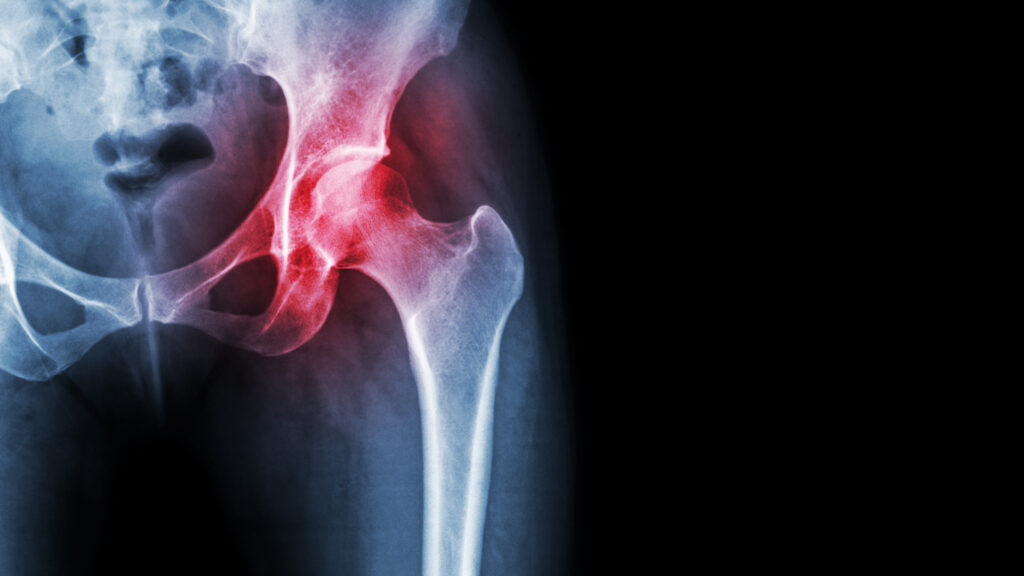

If you’re struggling with groin pain, hip flexor discomfort, or deep aches in the gluteal muscles, it can affect everything from walking to sleeping. At Wapping Chiropractic, we provide expert, non-invasive treatment for gluteal, hip, and groin pain in East London. Our care targets the root cause to reduce pain, improve mobility, and help you move freely again.

Understanding Gluteal, Hip & Groin Pain

Gluteal, hip, and groin pain may arise from a range of musculoskeletal issues, including: